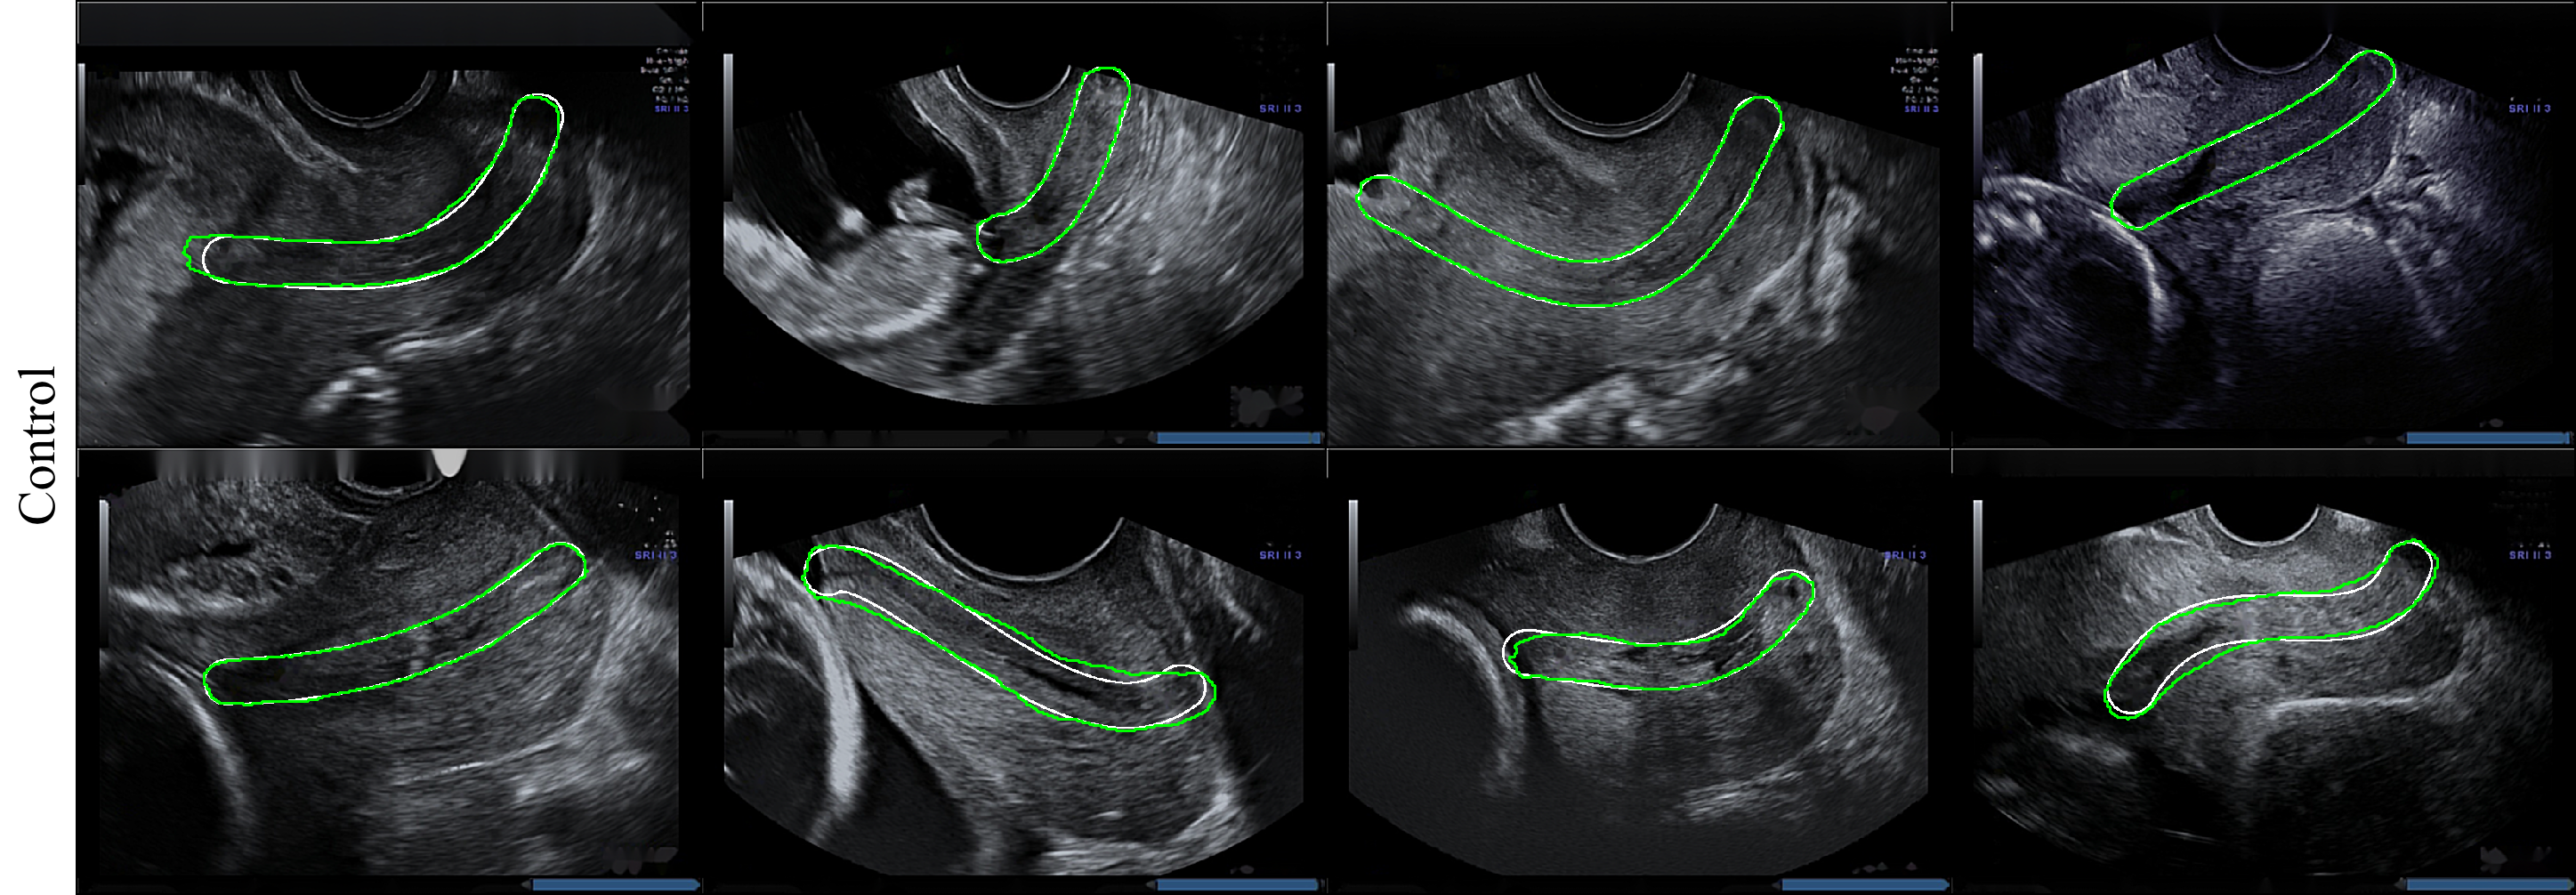

We achieved good segmentation results due to the easy structure of the cervix, which is relatively large in the ultrasound image. In Fig. 4 we show examples of retrieved cervix segmentation masks for each of the classes. From these examples, it can be seen that our proposed method was able to localise cervixes which are subject to variability in scale and appearance. Table 2 shows the quantitative performance of the proposed method in terms of mean std of IoU coefficient, precision, recall and AUC.

We validated three models against the cervix segmentation task applied to transvaginal ultrasounds images: FCN, DeepLab and U-Net. Visualization of results for segmentation are presented on Fig. 3. As shown in Table 1, the best performing results were achieved by U-Net. U-Net is built upon the architecture of FCN. Besides the increased network depth to 19 layers, U-Net benefits from a superior design of skip connections between different stages of the network. The most important advancement of U-Net over FCN is the shortcut connections between layers of equal resolution in the analysis path to expansion path. This gives U-Net better performance because it has multiple upsampling layers along with more skip connections which make it more robust to scale variations as compared to FCN.

We chose the U-Net based network for the classification task for several reasons. First, we obtained the best segmentation result qualitatively. The U-Net network best predicts edges that help us classify images based on the shape of the cervix. In addition, the U-net network contains the least parameters among the other networks tested, without requiring a large number of images and length of training to get a good performance.